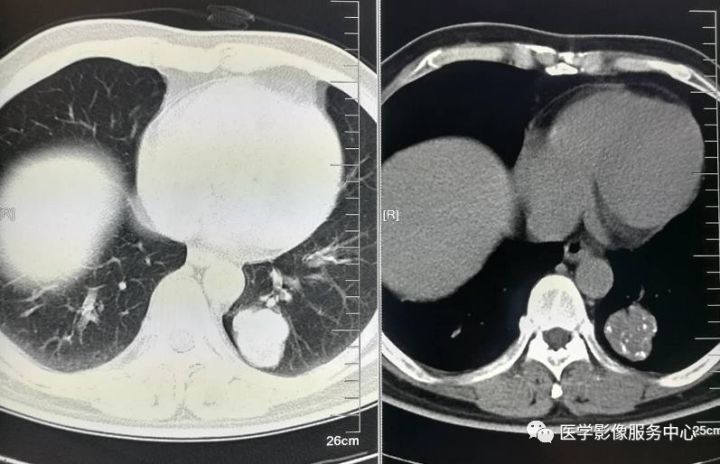

胸部CT平扫

胸部CT增强

CT表现:左肺下叶不规则肿块影,内见脂肪密度及多发钙化,增强扫描未见明显强化,纵隔未见肿大淋巴结。